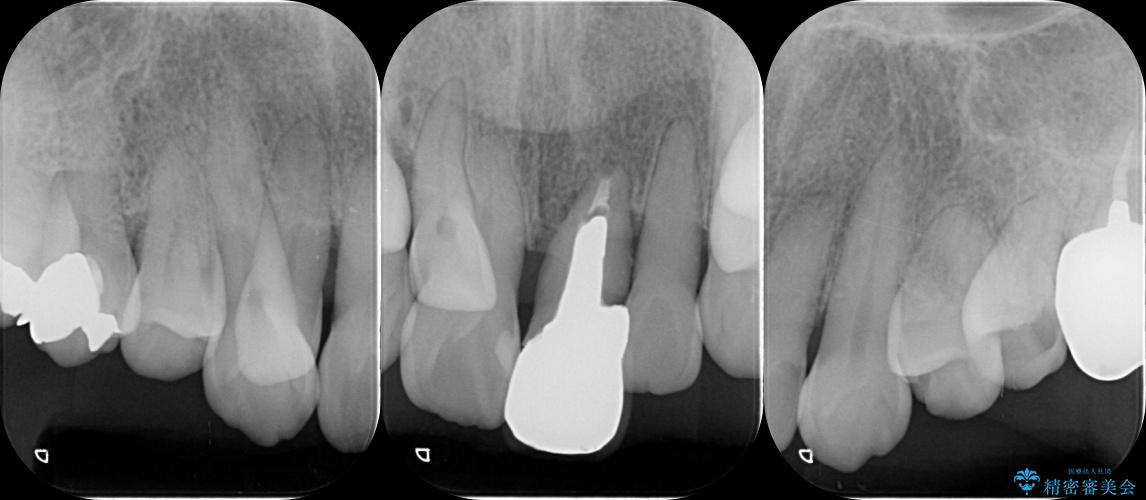

治療前

歯の総合的なマネージメントを行う包括的歯科治療の実践[ 歯周病・矯正・セラミック補綴 ] 治療前画像 歯の総合的なマネージメントを行う包括的歯科治療の実践[ 歯周病・矯正・セラミック補綴 ] 治療前画像 歯の総合的なマネージメントを行う包括的歯科治療の実践[ 歯周病・矯正・セラミック補綴 ] 治療前画像 歯の総合的なマネージメントを行う包括的歯科治療の実践[ 歯周病・矯正・セラミック補綴 ] 治療前画像 歯の総合的なマネージメントを行う包括的歯科治療の実践[ 歯周病・矯正・セラミック補綴 ] 治療前画像 歯の総合的なマネージメントを行う包括的歯科治療の実践[ 歯周病・矯正・セラミック補綴 ] 治療前画像 歯の総合的なマネージメントを行う包括的歯科治療の実践[ 歯周病・矯正・セラミック補綴 ] 治療前画像